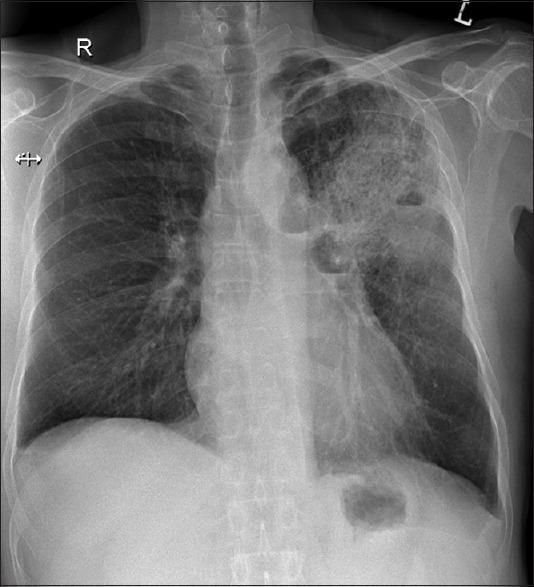

The 'crazy-paving' pattern on high resolution computed tomography (HRCT) is a distinct imaging appearance that is still considered to be a radiological hallmark of pulmonary alveolar proteinosis. However, since its first description about three decades ago, more than 40 different clinical entities presenting as 'crazy-paving' patterns have been documented. This rather remarkable but uncommon imaging appearance is now considered to be a non-specific manifestation. A 62-year-old male referred for evaluation of productive cough, breathlessness and fever presented with 'crazy-paving' pattern on HRCT. Endobronchial biopsy done on presentation was consistent with the diagnosis of squamous cell carcinoma. This report highlights this atypical presentation of squamous cell carcinoma of the lung and adds to the increasing list of clinical entities presenting as a 'crazy-paving' pattern. To our knowledge, squamous cell carcinoma presenting as a 'crazy-paving' pattern on HRCT is yet to be documented.